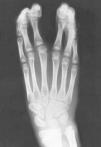

Figura 3. Caso 3. Pentadactilia con hipoplasia del dedo más radial, trifalángico. Ausencia de musculatura tenar.